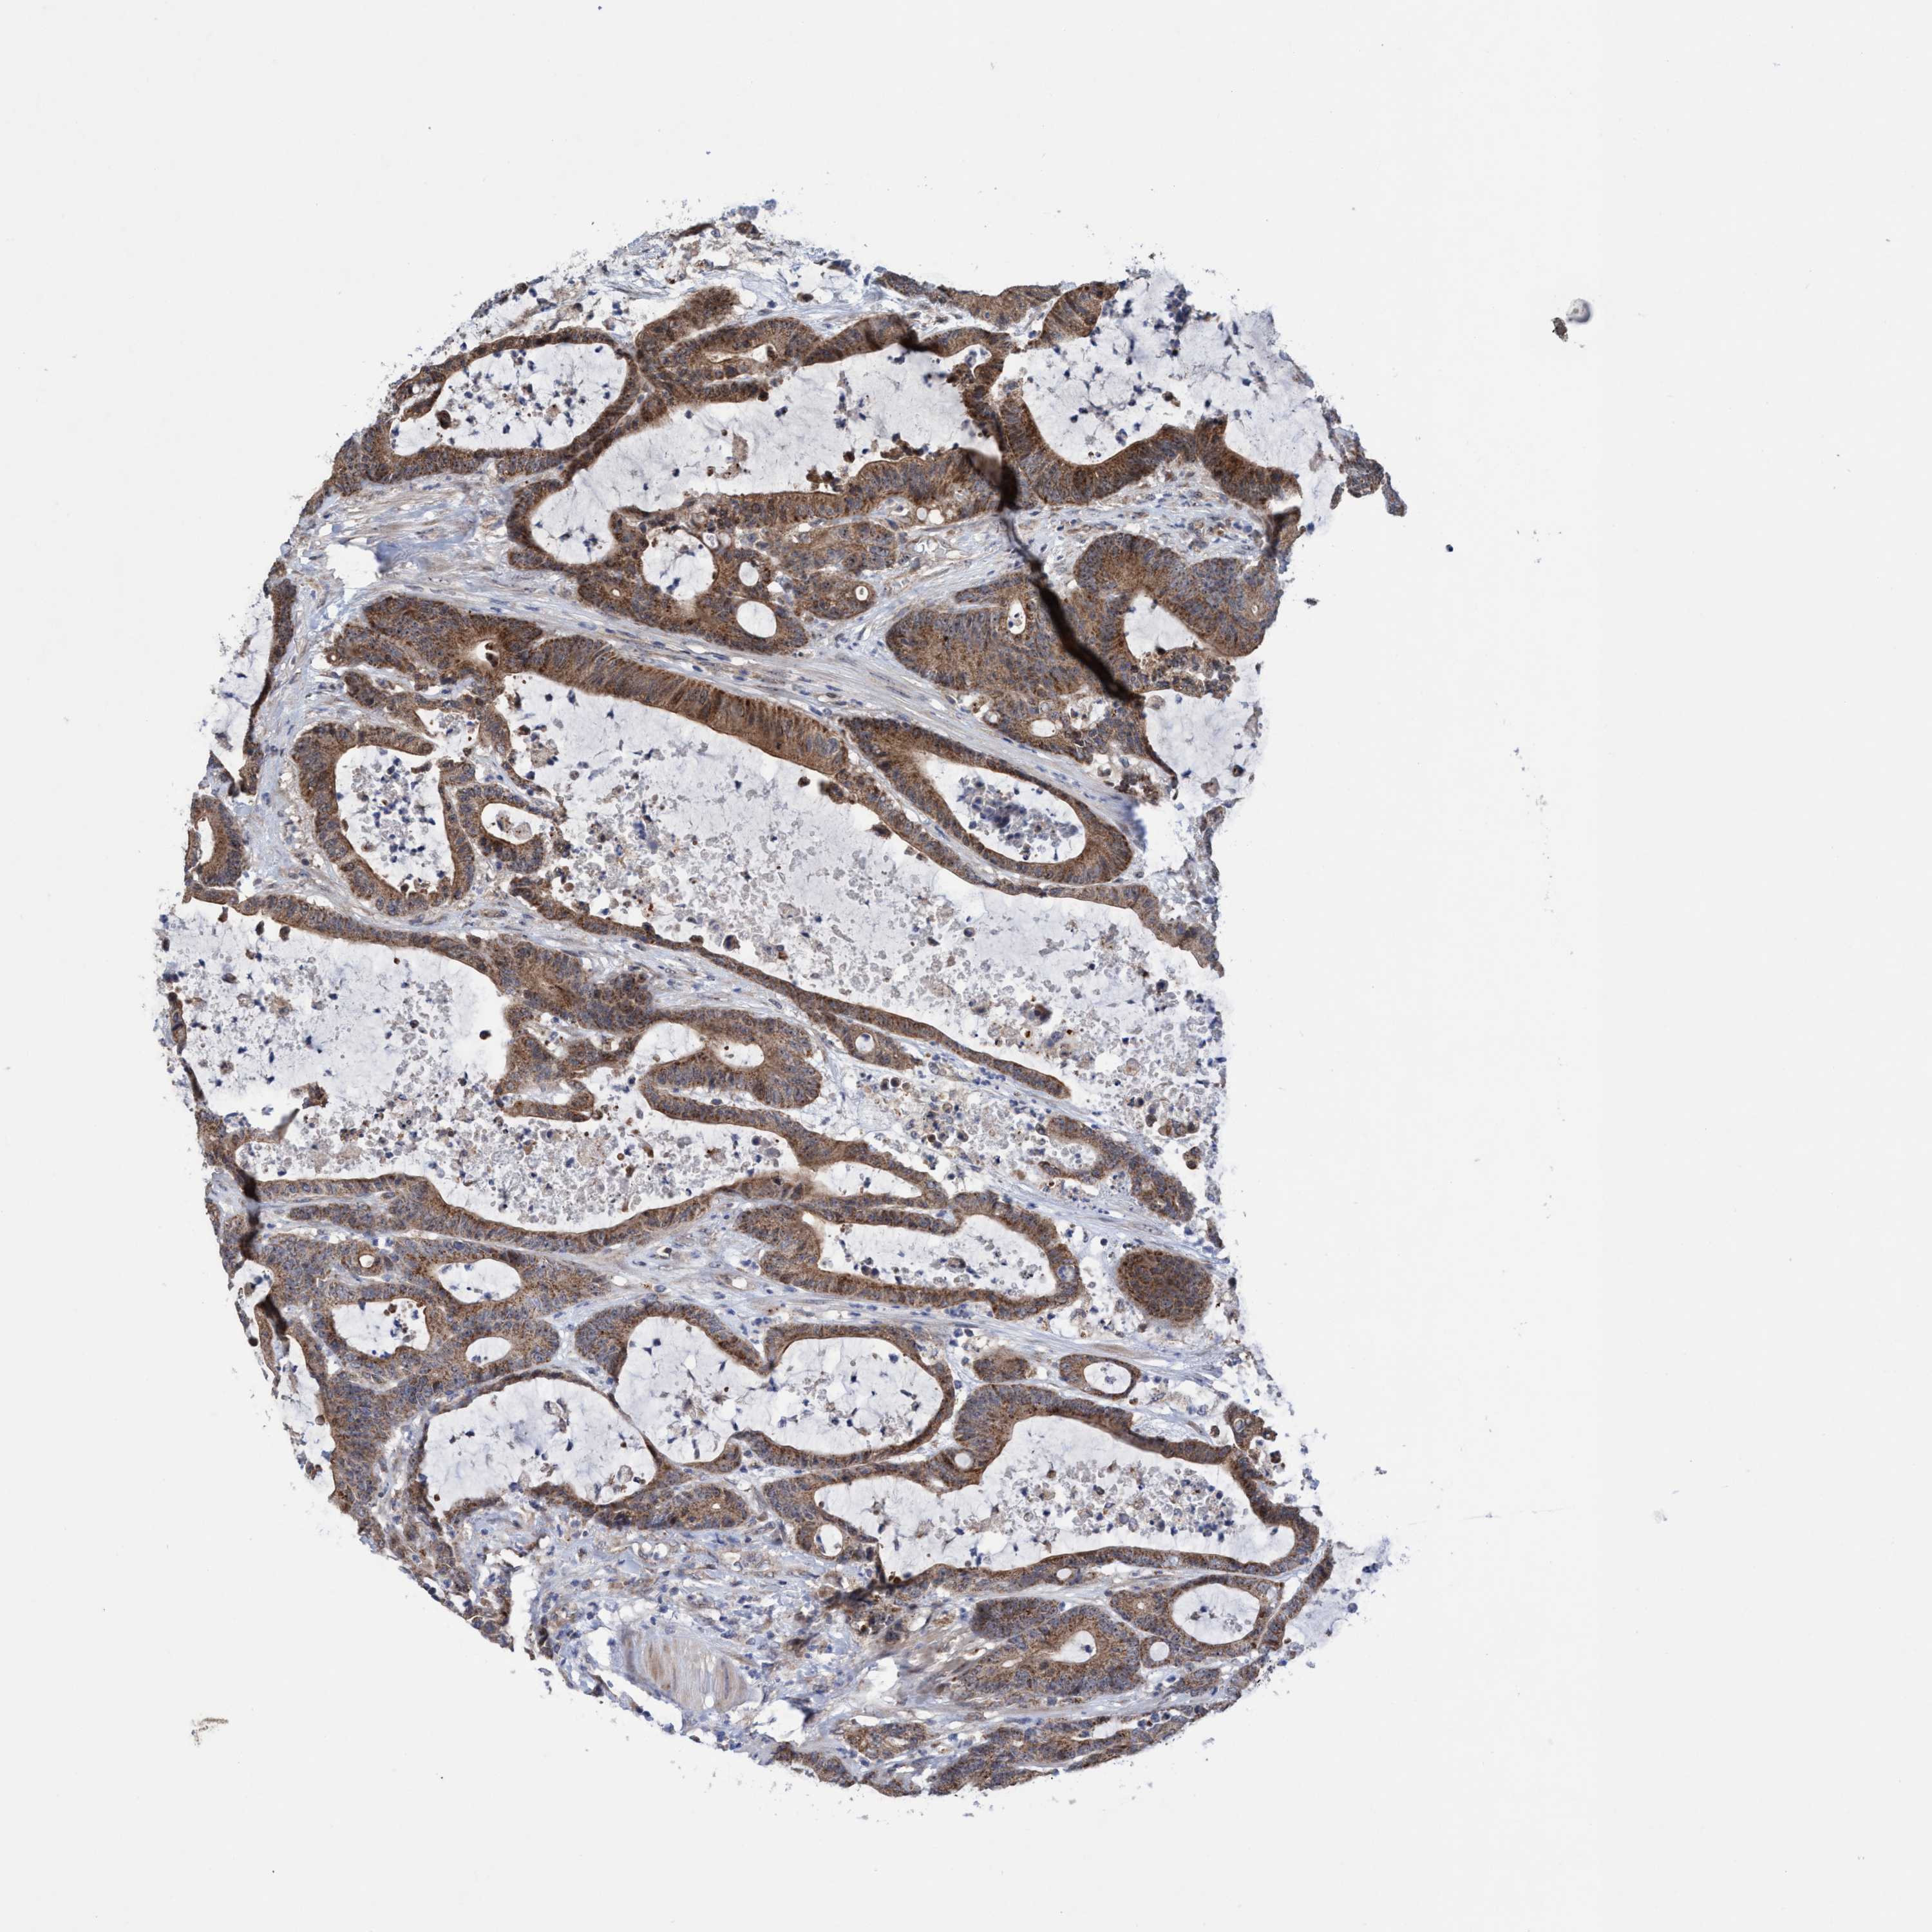

ANTIBODIES

AND

VALIDATION